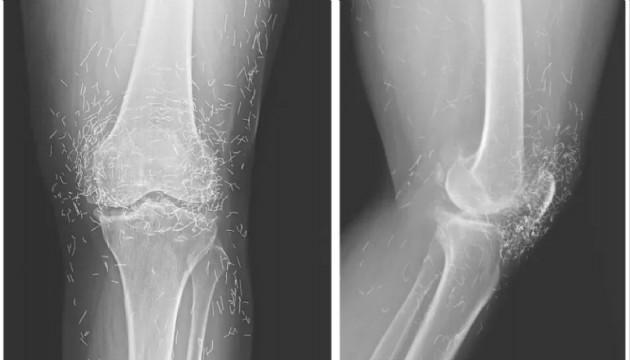

65 yaşındaki Güney Koreli bir kadın, şiddetli diz ağrıları nedeniyle hastaneye başvurduğunda röntgeninde yüzlerce altın iplik görüldü.

Hastanede yapılan tetkikler sonucunda, röntgendeki altın ipliklerin, kadının düzenli olarak uygulattığı altın iplik akupunkturu seanslarında bilerek bırakıldığı öğrenildi. Bu uygulamada steril kısa altın iplikler dokuya yerleştirilerek sürekli uyarım sağlanması amaçlanıyor.

Ayrıca bu ipliklerin görüntüleme teknikleri üzerinde de olumsuz etkileri olabiliyor. Röntgenlerde yorumlamayı zorlaştırmasının yanı sıra, manyetik rezonans (MR) görüntülemelerinde ipliklerin hareket etmesi ve damarlara zarar vermesi riski bulunduğu vurgulandı.

Doktorlar, bu tür geleneksel tedavi yöntemlerine başvuran hastalarda altın ipliklerin varlığının mutlaka göz önünde bulundurulması gerektiğini belirtiyor. Neyse ki ipliklerin röntgende rahatça görülebilmesi sayesinde konumları zamanla takip edilebiliyor.